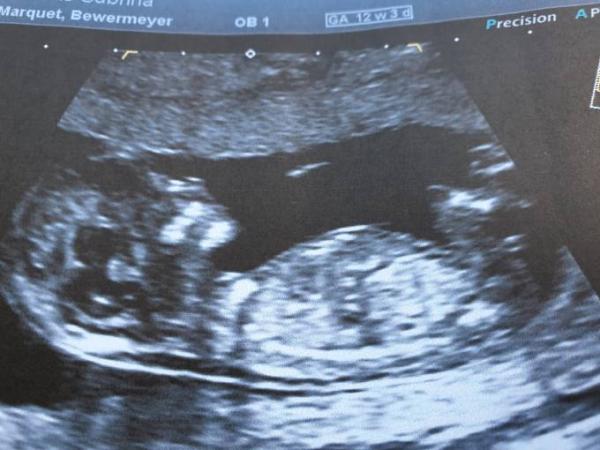

Hallo aus dem Dezemberbus, Ja sie dürfen es vor der 14. SSW nicht sagen. Jedoch gab unsere Ärztin uns einen kleinen Hinweis. Mit einem Augenzwinkern bat sie "den kleinen Mann" doch mal etwas still zu halten. Das hat sich in den letzten Wochen natürlich bestätigt, wir freuen uns auf unseren kleinen Buben Bei uns war das bei 12+3 und es wurde ausgiebig ein normaler Ultraschall gemacht, die Gerätschaften sind allerdings viel genauer als in der normalen FA-Praxis. Man kann echt supiviel erkennen. Als Erinnerung gab es natürlich auch ein Bild zum mitnehmen. Ich hoffe, das hilft dir weiter :-)

Bild zu